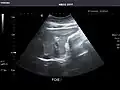

Spleen: Normal in size.

Spleen -